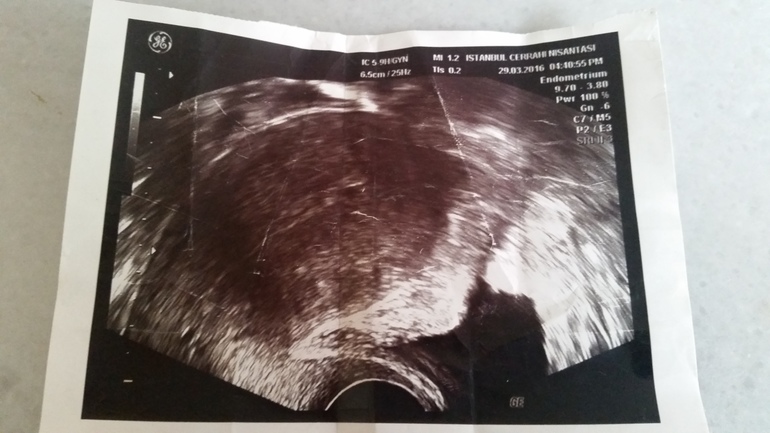

Обратилась спустя выходные в другую клинику, доктор проведя внутривагинальное узи в первую же минуту увидела точку в матке . День цикла был 29 , задержки не было.

Поставила вероятность беременности 80% и срок около 2-3 недель с большой вероятностью выкидыша отправила на хчг.

у вас в матке слизистое скопление...по снимку видно... поэтому вы мажете так часто..это не страшно я забеременнела практически на фоне подобного....но вам лечение и наблюдение необходимо!!!!

При хгч 2 плодное яйцо увидеть невозможно, поэтому эта точка точно не Б, к сожалению.

если точка это плодное яйцо,то хгч был бы уже больше 1000